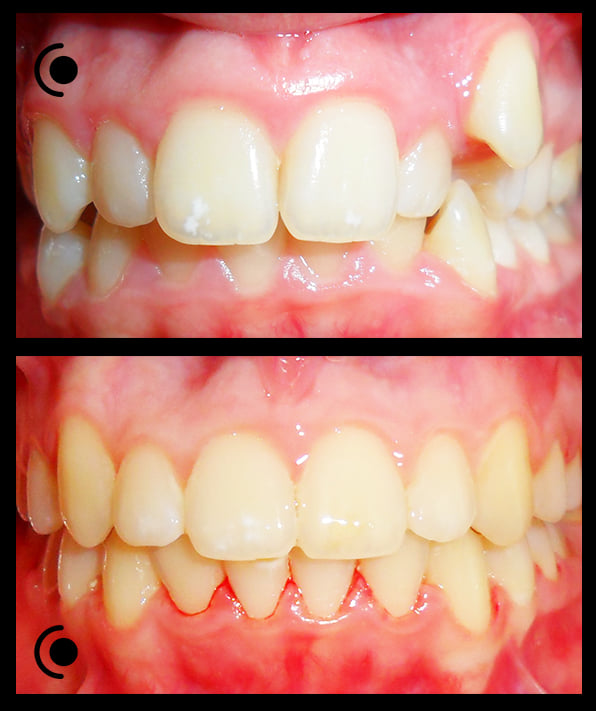

O našoj kvaliteti najbolje govore naši rezultati!